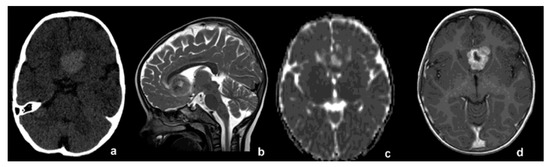

2. Case Report